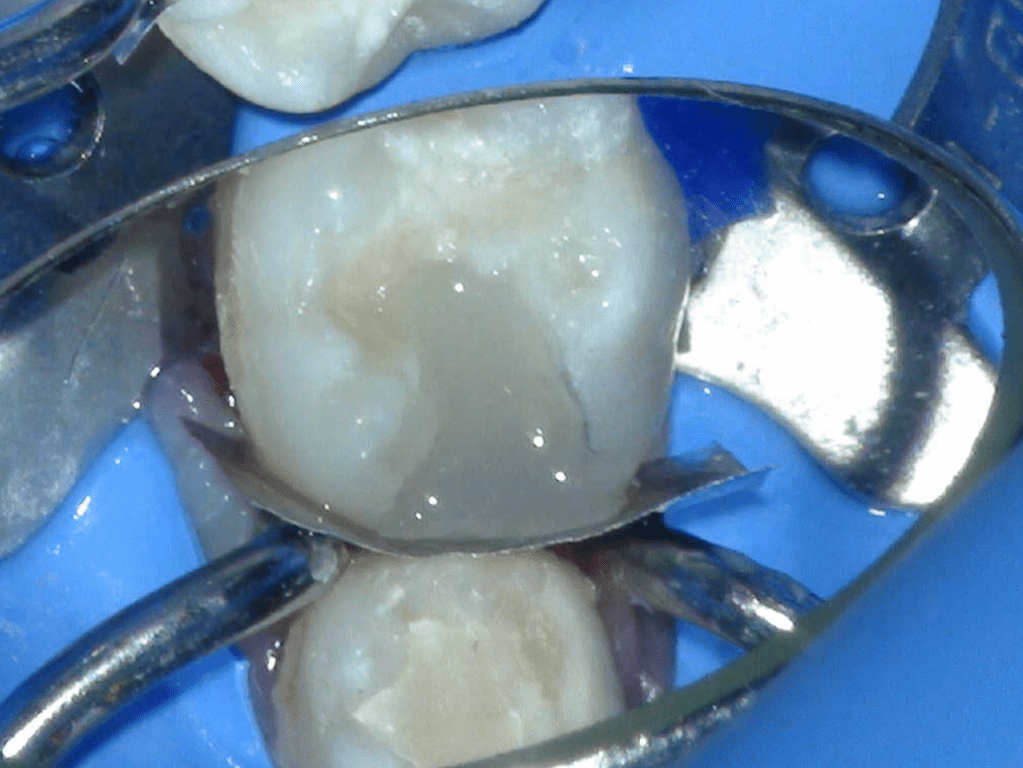

Reconstrucción preendodóntica

Reco pared vesticular